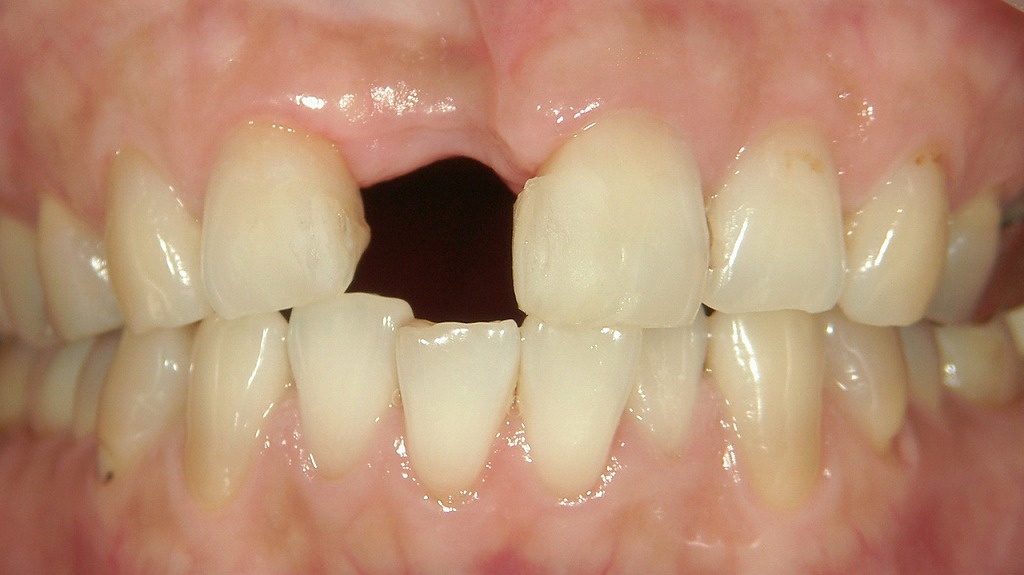

■ 右上前歯の欠損:インプラント治療を検討するべき状態

画像は上顎前歯部を正面から撮影した口腔内写真で、右上顎中切歯(1番)が欠損している状態です。

■ インプラント治療を計画する際のポイント

- 骨量の確認が必須

前歯部インプラントは審美性の要求が高いため、CTによる骨量(特に唇側骨)の精査が重要です。

必要に応じてGBR(骨造成)を併用するケースもあります。 - 歯肉形態の調整が重要

歯肉ラインを左右差なく整えるため、結合組織移植や歯肉ボリュームの調整を行うこともあります。 - 隣接歯とのバランスを精密に管理

特に中切歯は対称性が求められ、インプラントポジション・アバットメント形態・最終補綴物のシェード選定が仕上がりに大きく影響します。 - 補綴前のスペース調整

歯列の軽度の叢生や傾斜がある場合、インプラント位置確保のため軽度の矯正治療を併用することも検討されます。